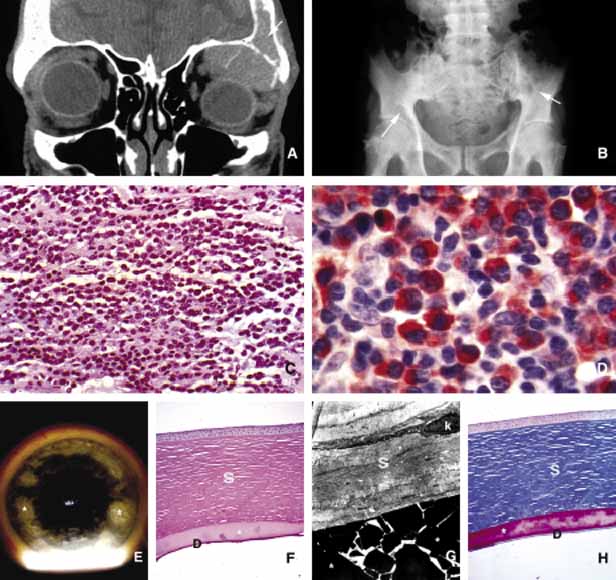

Fig. 7 Orbital tuberculosis. A 2-year-old boy with left orbital tuberculosis (A). Both mother and child had systemic disease. A case of bilateral orbital and perinasal sinus tuberculosis is shown in the coronal CT of a 28-year-old man (B). Note the irregular involvement of the bony tissues of the orbits and the sinuses. C and D show a caseating granuloma (c) and AFB-positive tuberculous bacilli in necrotic inflammation (arrowheads) respectively.